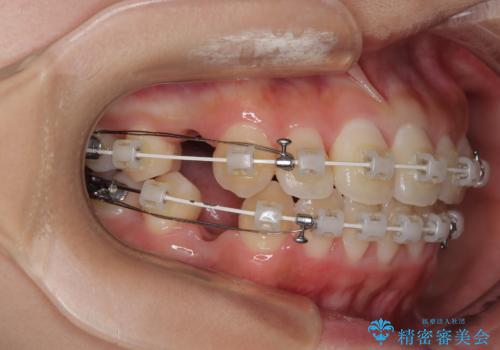

急速拡大装置 狭い骨幅を拡大した上で、口元の突出感を改善する抜歯矯正治療

単純に上下左右の第一小臼歯4本を抜歯して口元の突出感を改善することも考えられましたが、上顎骨よりも下顎骨の幅が広いため、より良い咬み合わせを達成することを目的として、急速拡大装置を用いて上顎骨を拡大することとしました。

歯列矯正では基本的に骨格を改善することはできませんが、急速拡大装置(MARPE)を使用することで上顎骨を側方に拡大させることができ、咬合状態を大きく改善することができます。